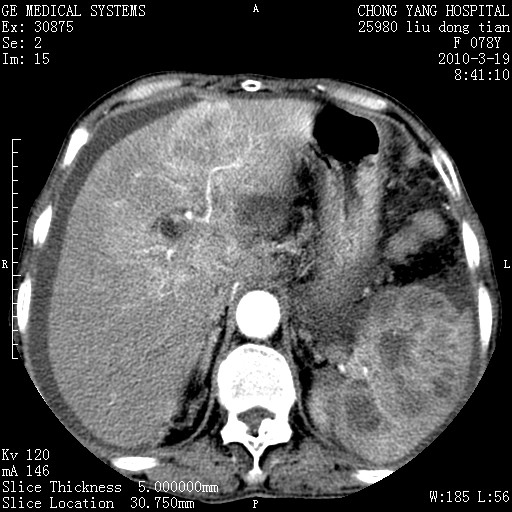

标题: CT25199:F 78Y 腹胀半年 消瘦乏力 [打印本页]

胰头有肿块形成,胰头ca伴肝脾、腹膜腹膜后转移

胆囊有软组织影有强化,支持胆囊癌,肝脾、腹膜后淋巴结转移。

分开来讲:肝左叶、尾叶病灶有不均强化像肝癌;

脾脏病灶无强化,像多发囊肿或淋巴管瘤,不除外淋巴瘤(低强化);

肝门、胰腺头、腹膜后多个团块: 淋巴瘤,转移;

脾脏病灶像车轮 莲花,第一感觉还像包虫呢。真想全切出来一个个做病检。

胰头ca伴肝脾、腹膜腹膜后转移!

最后报的胰头癌多发转移,脾脏单独考虑囊肿或淋巴管瘤。